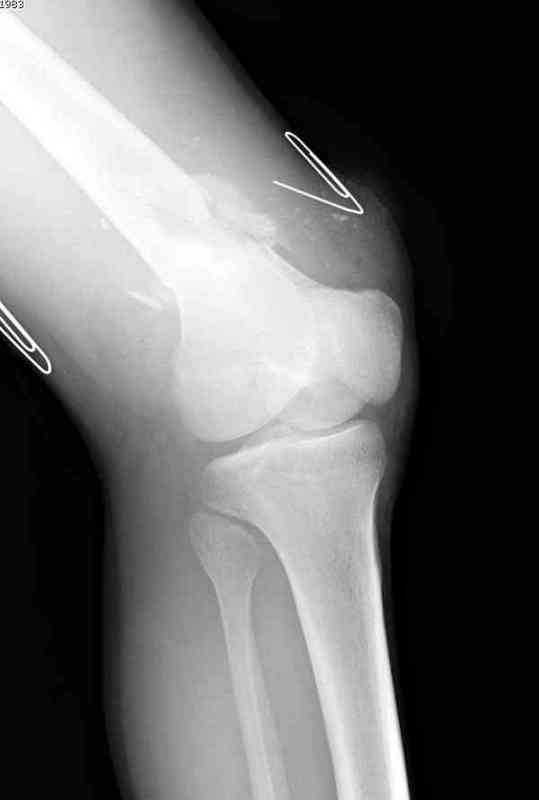

Вчера утром поступил больной с огнестрельной раной, осмотрен сосудистым специалистом, сделана ангиограмма (снимки) Во время операции при вскрытии обнаружили кровотечение, рану забили салфетками, установили пластину locking DePuy.

Из-за возрастающего давления в компартменте сделана фасциотомия и вызванный сосудистый хирург ушил разрыв вены на уровне перелома. Все раны оставлены открытими, в пятницу закроем.